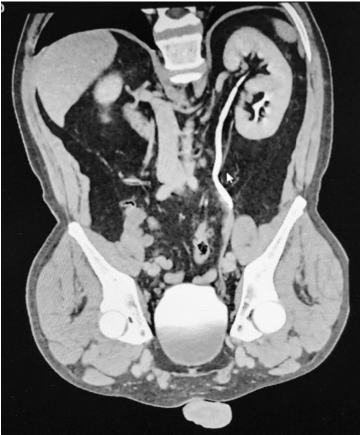

En la uro tomografía contrastada realizada, en fase excretora, se evidenció que el riñón izquierdo tenía 2 uréteres (Figura 1 y Figura 2), por lo cual se solicitó opinión del servicio de Urología, no hallándose contraindicación con el uso de ese riñón para el trasplante renal.  Posteriormente, al momento de la intervención quirúrgica, se implantaron ambos uréteres con la técnica de “cañón de escopeta” en la vejiga del receptor.

Figura 1. Tomografía abdominal del donante en fase excretora

Figura 2. Riñón del donante con los 2 uréteres